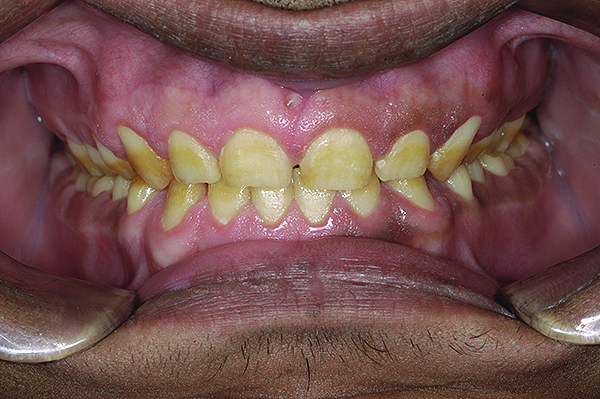

Figure 14. 1:2 retracted frontal view with provisionals in MIP.

Figure 14

After the material had set, the index was removed. A correctly fabricated index will show a thin uniform flash of excess material, which, in this case, was carefully peeled off and cut with a sharp #12 blade. The provisionals on the lower jaw were fabricated in a similar manner. Once the gross excess was removed, the patient was guided to close in MIP, with the condyles guided to CR. The occlusal contacts were then marked and adjusted until uniform contacts of equal intensity were achieved on both sides and anterior guidance was sufficient to disclude posteriors in all eccentric mandibular positions (Figure 13 and Figure 14).

At this juncture, an evaluation of the esthetics, phonetics, VDO, and all other macro and micro elements15 of smile design should be verified. Any changes—additive or subtractive—can be carried out in the patient’s mouth itself. The full-face smile photographs and close-up views were taken and evaluated. The patient was asked to “test drive” the provisionals for a few weeks and report with any feedback so that necessary corrections could be carried out. At this time, even the functional aspects can be verified, and a transcranial radiograph or a CBCT scan may be taken to verify the position of condyle in the glenoid fossa.